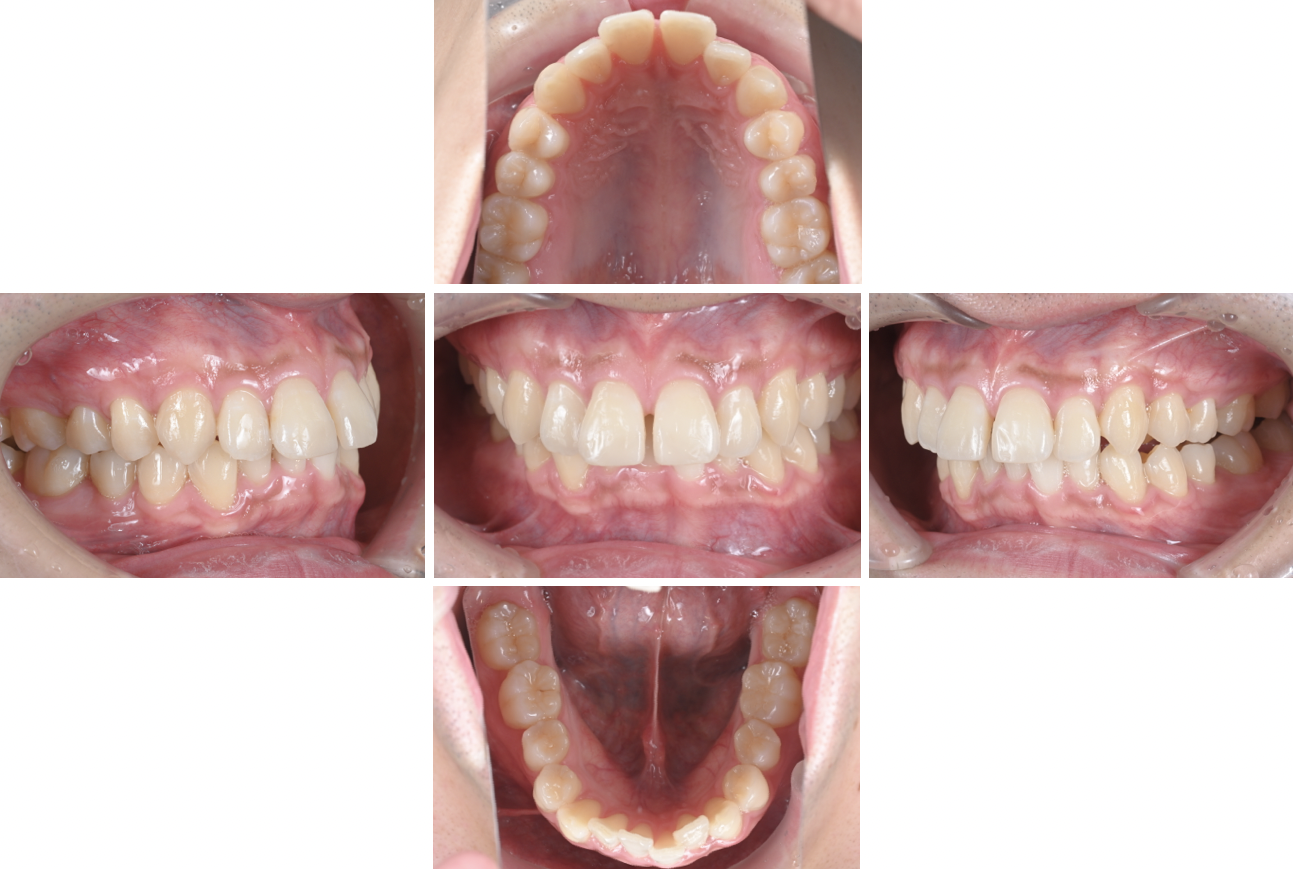

《初診時》

上の前歯が欠けており、ダイレクトボンディングをご希望でした。

しかし、噛み合わせそのものを正さなければ、また欠けてしまい、その度費用がかかってしまいます。

矯正歯科治療をご提案したところ、マウスピース矯正も頑張ってくださることになりました。

《ダイレクトボンディング終了時》

まずはダイレクトボンディングで綺麗に整えました。